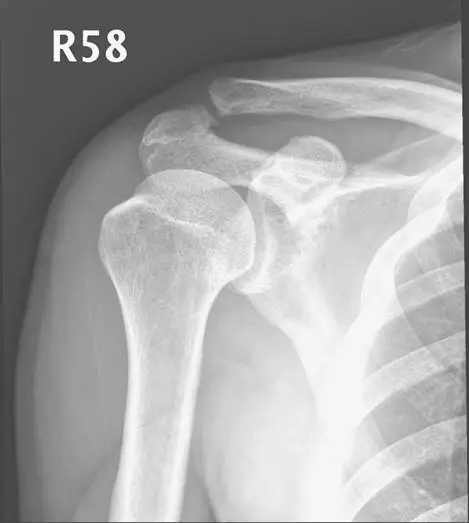

51 歲男性病人,右側肩膀疼痛,且轉動受限。超音波及 X光片檢查如圖,最可能的診斷為何?

上圖(超音波,RT SS TR): 右肩棘上肌腱橫斷面(short axis transverse)超音波影像。影像右上角顯示探頭設定(Small P, 12.50-3.00 MHz,MI 0.9)。可見:

- 肱骨頭(humeral head)弧形高回音骨皮質清晰可見於下方

- 骨皮質上方出現一層均勻低回音/無回音液體帶(anechoic fluid layer)

- 影像中可見測量標記(

+...+),標示積液厚度 D1 = 0.556 cm(約 5.6 mm) - 正常肩峰下-三角肌下滑液囊(subacromial-subdeltoid bursa)厚度 < 2 mm;本圖 5.6 mm 顯著超過正常值,確認滑液囊異常積液擴張

- 棘上肌腱本身(三角肌與液體帶之間)回音尚可辨識,未見明顯全層缺損,與旋轉環帶斷裂的無回音缺損不同

- 液體帶內無高回音鈣化沉積,排除鈣化物遷移至滑液囊

下圖(X 光,R58): 右肩關